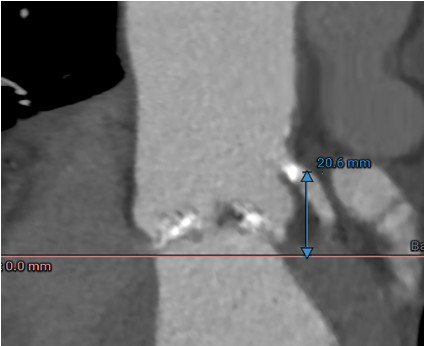

冠脉高度测量

LEFT CORONARY

左冠开口高度20.6mm

RIGHT CORONARY

右冠开口高12.6mm